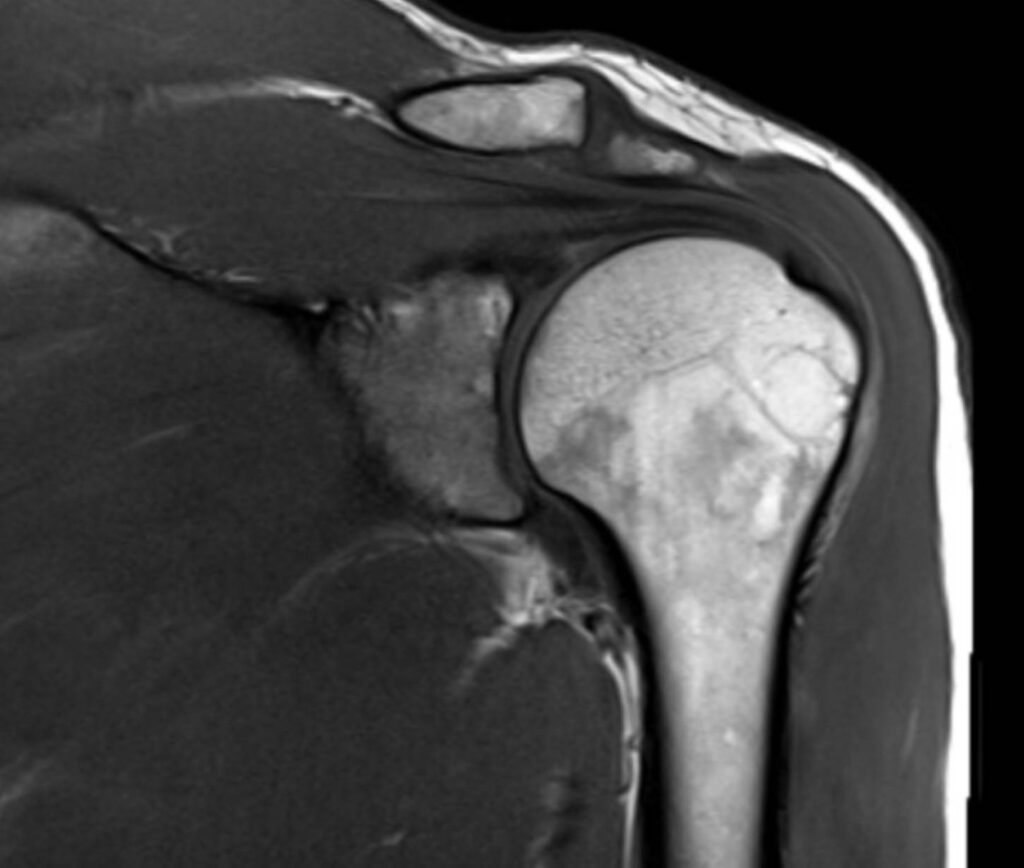

Die Magnetresonanztomographie der Schulter, kurz MRT Schulter genannt, ist eine bildgebende Untersuchung, die detaillierte MRT Bilder der Schulterstrukturen liefert, ohne Röntgenstrahlen zu verwenden. Sie ermöglicht die präzise Diagnose von Schulterschmerzen, Verletzungen, Arthrose und weiteren Erkrankungen der Schulter.

Eine Magnetresonanztomographie (MRT) oder auch Kernspintomographie der Schulter ist eine schmerzlose bildgebende Untersuchung, die ermöglicht die Strukturen im Schulterbereich präzise darzustellen. Es handelt sich hierbei um Querschnittbilder, die mithilfe von Magnetfeldern und Radiowellen ohne den Einsatz von ionisierender Strahlung erstellt werden. Mit der MRT können Knochen, Weichteile wie Muskeln und Sehnen, Gelenke sowie Nerven und Blutgefäße in der Schulterregion abgebildet werden. Dies ermöglicht die Diagnose von Schulterschmerzen, Verletzungen, Arthrose, Entzündungen und anderen Erkrankungen.

Was sieht man bei einer MRT Schulter?

| Gelenke und Knochen | Frakturen, Arthritis, weitere Gelenk-/Knochenprobleme |

| Bänder und Sehnen | Verletzungen oder Entzündungen |

| Schleimbeutel | Entzündung oder Schwellung |

| Rotatorenmanschette | Verletzungen oder Risse |

| Labrum | Verletzungen oder Risse |

| Nerven und Blutgefäße | Nervenkompression oder Gefäßveränderungen |